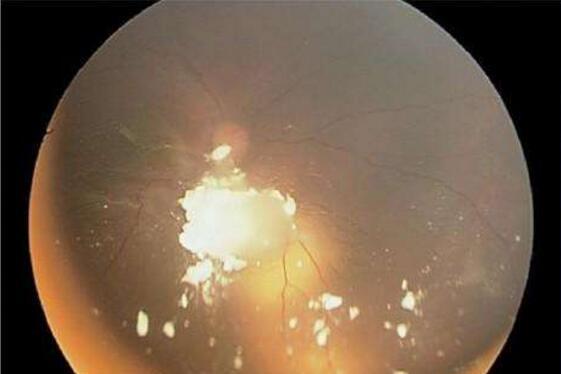

1、白瞳征:成年白内障患者,常常因视力明显减退而就诊,而婴幼儿白内障患者,特别是单眼患者,一般并无症状,因此经常被延误诊断,只有当瞳孔区出现白色反光,即所谓白瞳征(leukokoria)时,方引起家长或医生的注意,白瞳征并非先天性白内障所特有,临床上应与其他病症加以鉴别。

5、合并的其他眼部异常:先天性白内障合并先天性小眼球临床并不罕见,先天性小眼球的存在与白内障类型无关,且常合并其他眼组织发育异常,如脉络膜缺损,视力预后极差,即使手术也不能获得满意的视力结果。